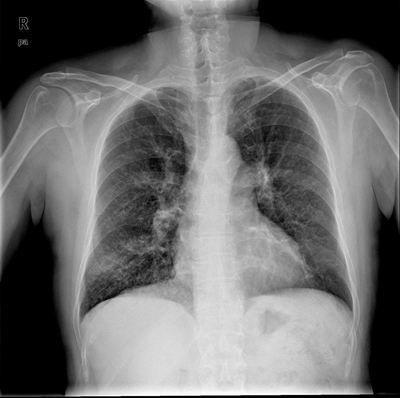

患者,男,60岁,病史如下:

2008.5.16胸片